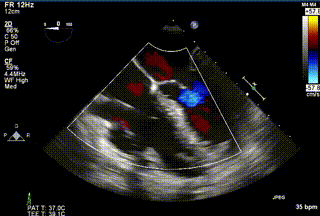

2021年12月24日,復(fù)旦大學(xué)附屬中山醫(yī)院葛均波院士團(tuán)隊(duì)成功應(yīng)用LuX-Valve Plus為一例極重度三尖瓣反流(TR)合并房顫、房缺的患者完成了經(jīng)血管三尖瓣置換術(shù),這是在前基礎(chǔ)上,本周完成的第三例經(jīng)血管三尖瓣置換手術(shù),葛均波院士、周達(dá)新教授等與心外科魏來教授、賴顥教授,心超室的潘翠珍教授、李偉教授及麻醉科的郭克芳教授共同完成了本周手術(shù),均獲得圓滿成功!患者術(shù)后超聲顯示無TR,臨床癥狀明顯改善。本周手術(shù)的成功也為L(zhǎng)uX-Valve Plus救治性臨床研究添上了濃墨重彩的一筆。

三例患者入院后,葛均波院士團(tuán)隊(duì)周達(dá)新教授、潘文志教授、張?jiān)床┦俊㈥惿┦考靶某业呐舜湔浣淌?、李偉教?/strong>對(duì)患者的情況進(jìn)行詳細(xì)評(píng)估和討論,最終決定為三例患者選擇LuX-Valve Plus40mm、50mm和50mm型號(hào)的瓣膜進(jìn)行手術(shù)治療。手術(shù)后即刻拔除氣管插管,術(shù)后患者三尖瓣反流癥狀得到顯著改善,復(fù)查心超結(jié)果顯示人工三尖瓣瓣膜支架固定穩(wěn)定,瓣葉關(guān)閉形態(tài)未見異常,未見明顯反流。